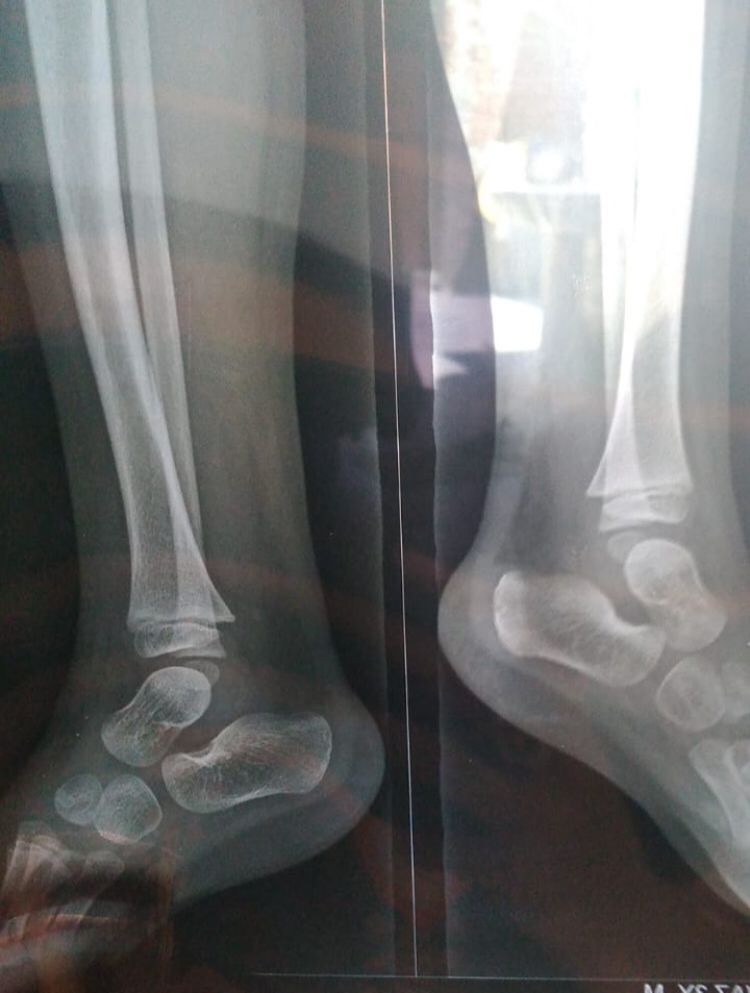

Please have a look at his x-ray

Please have look his x-ray

x-ray

please have a look his x-ray report